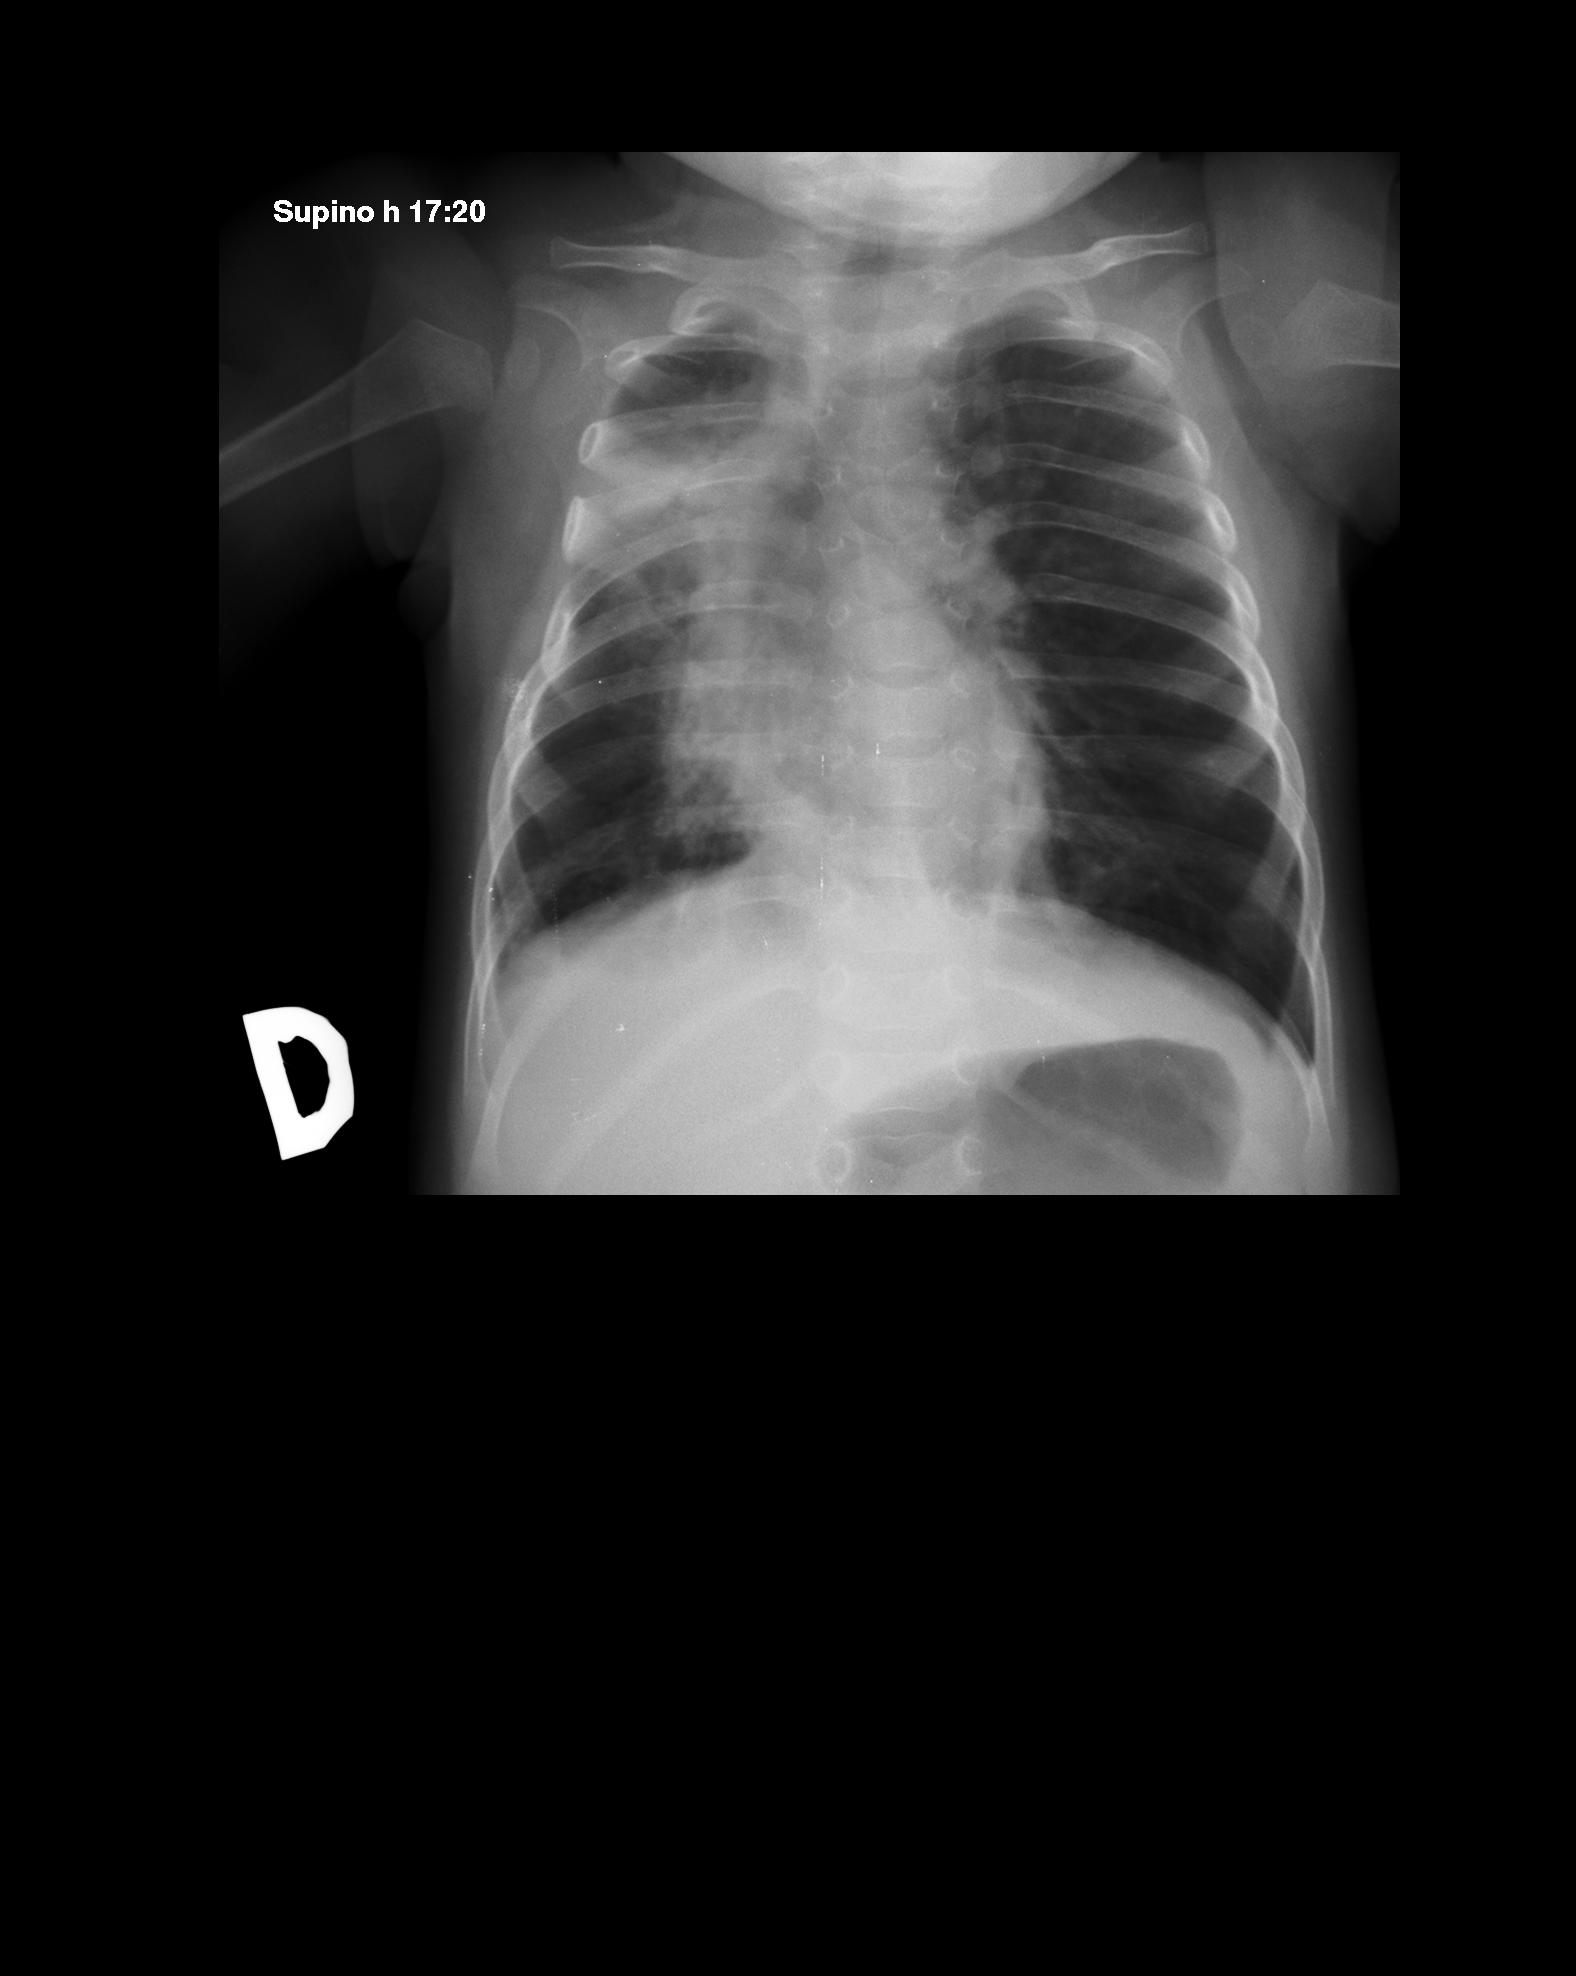

Un lattante di 6 mesi affetto da atrofia muscolare spinale di tipo 1 viene ricoverato per un episodio di broncopolmonite, resistente alla terapia antibiotica orale avviata a domicilio e caratterizzato da quadro di importante impegno respiratorio. All'ingresso � febbrile, polipnoico, dispnoico con moderata desaturazione arteriosa di ossigeno (91%), ma reattivo e con tempo di ricircolo capillare nella norma. Il fabbisogno di ossigeno � di 3 l/min con occhialini. Al torace si apprezzano rumori trasmessi dalle alte vie aeree associati a ronchi, rantoli umidi ed espirio prolungato. L'emogasanalisi capillare mostra pH 7,41, pCO2 44,2 mmHg, pO2 62 mmHg, bicarbonato 28,6 mEq/l, BE 4. La radiografia del torace evidenzia un'atelettasia destra con spostamento del polmone controlaterale (Figura 1).

La

Figura

1. Radiografia del torace che evidenzia: marcato spostamento del

mediastino, deviazione dell'asse tracheale, erniazione del polmone

sinistro a destra; opacamento del campo polmonare medio e superiore

di destra con atelettasia del lobo superiore. Figura